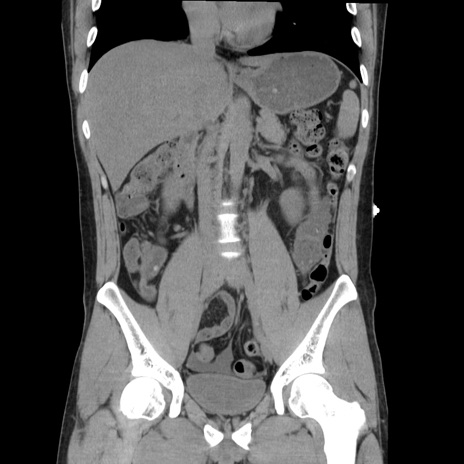

症例36(冠状断像)

【症例】20歳代 男性

【主訴】心窩部痛

【現病歴】今朝より上腹部痛あり。一旦軽快していたが再度出現したため救急要請。昨日夕に白身の魚を含む刺身を食べた。

【身体所見】BP 136/89mmHg、HR 74/min、BT 37.0℃、腹部:膨満、軟、心窩部に圧痛あり。反跳痛なし、筋性防御なし、腸雑音やや亢進あり。

【データ】WBC 17700、CRP 0.48